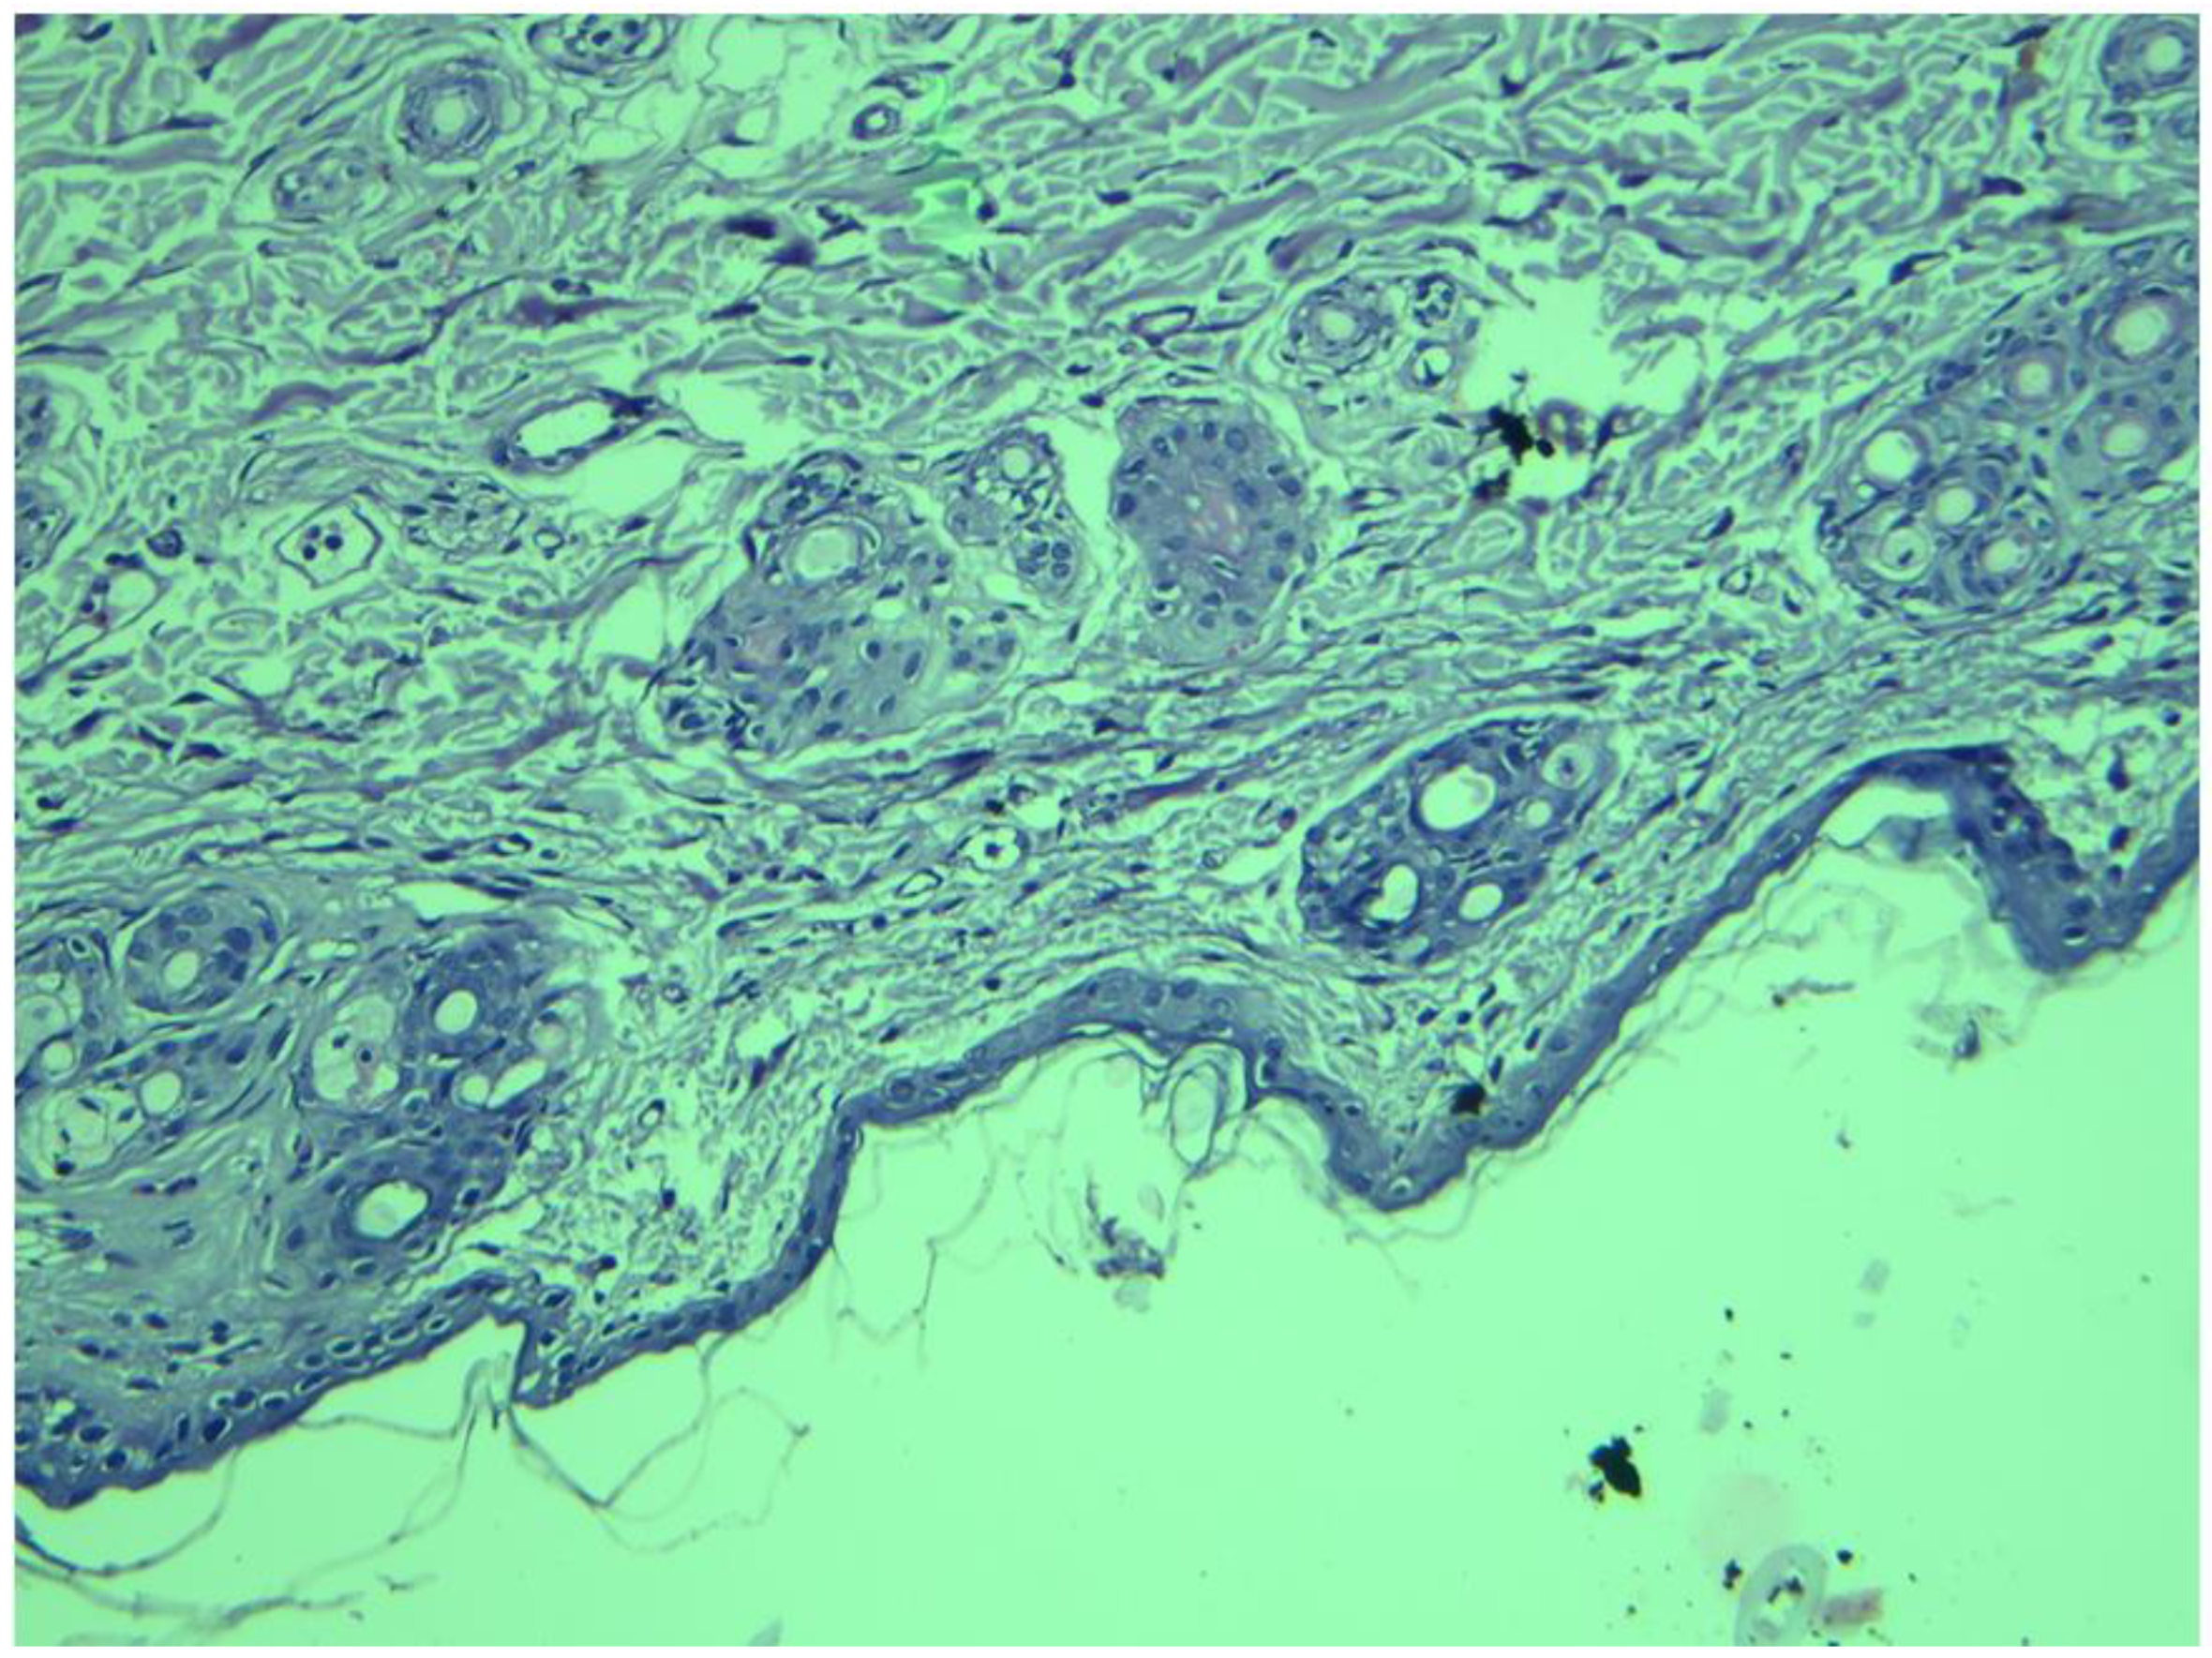

3.8. Histopathological Examination